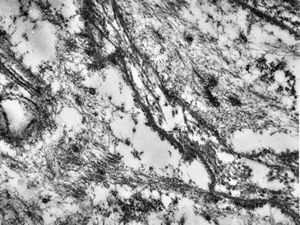

F,32y. | transversally sectioned skeletal muscle cell

mouse skeletal muscle cell - transversal section